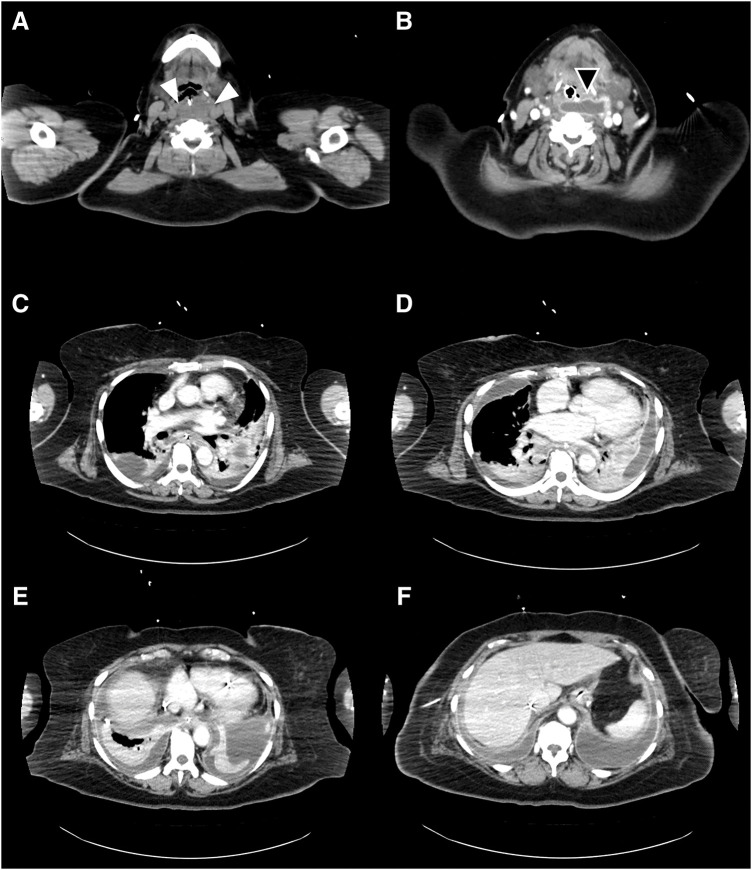

Case presentation: A female patient with morbid obesity (body mass index, 41 kg/m2) and a heavy smoking habit underwent laparoscopic sleeve gastrectomy and was discharged without any immediate postoperative complications. Six weeks later, the patient presented with severe chest and back pain that required continuous fentanyl injection for pain management. Initially, staple line leakage, commonly observed after sleeve gastrectomy, was suspected. However, her condition progressively worsened, and she was admitted to the ICU. An enhanced abdominal CT scan extending to the cervical region revealed a cervical abscess extending to the lower mediastinal region. The patient was diagnosed with descending necrotizing mediastinitis. Given the rarity of this disease, we hypothesized that her smoking habits exacerbated the piriform fossa injury caused by the calibration tube used during gastrectomy. Following the diagnosis, emergency abscess drainage surgery was performed, and the patient was successfully treated.

Conclusions: This is the 1st reported case of descending necrotizing mediastinitis as a fatal complication of laparoscopic sleeve gastrectomy, which was identified and treated successfully owing to the timely and expanded use of an enhanced CT scan that included the cervical region. Traditionally, the cervical area has not been routinely examined when diagnosing complications following abdominal surgery, underscoring the importance of a comprehensive imaging approach from the neck to the abdomen to detect complications after sleeve gastrectomy.